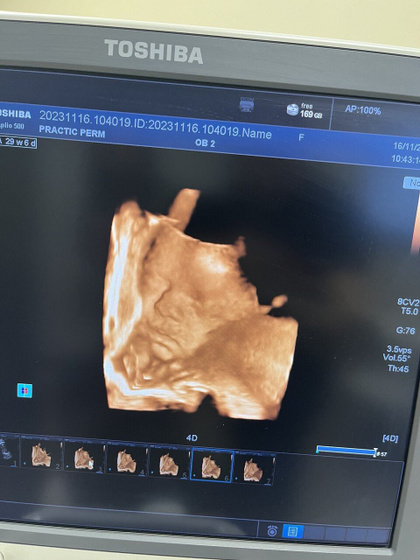

30 недель ) начала декрета, а он у меня не скоро ? самый хлеб декабрь для бьюти мастеров ) работаю до 30.12. Ходила сегодня на последний скрининг и смотрела на своего сыночку ?❤️ первое фото сын второе фото дочка( в профиль) 7 лет назад в 30 недель. Совсем разные)))

Простите загрузилось на первом дочь на второй сын